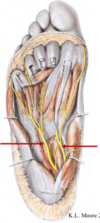

Identifiez